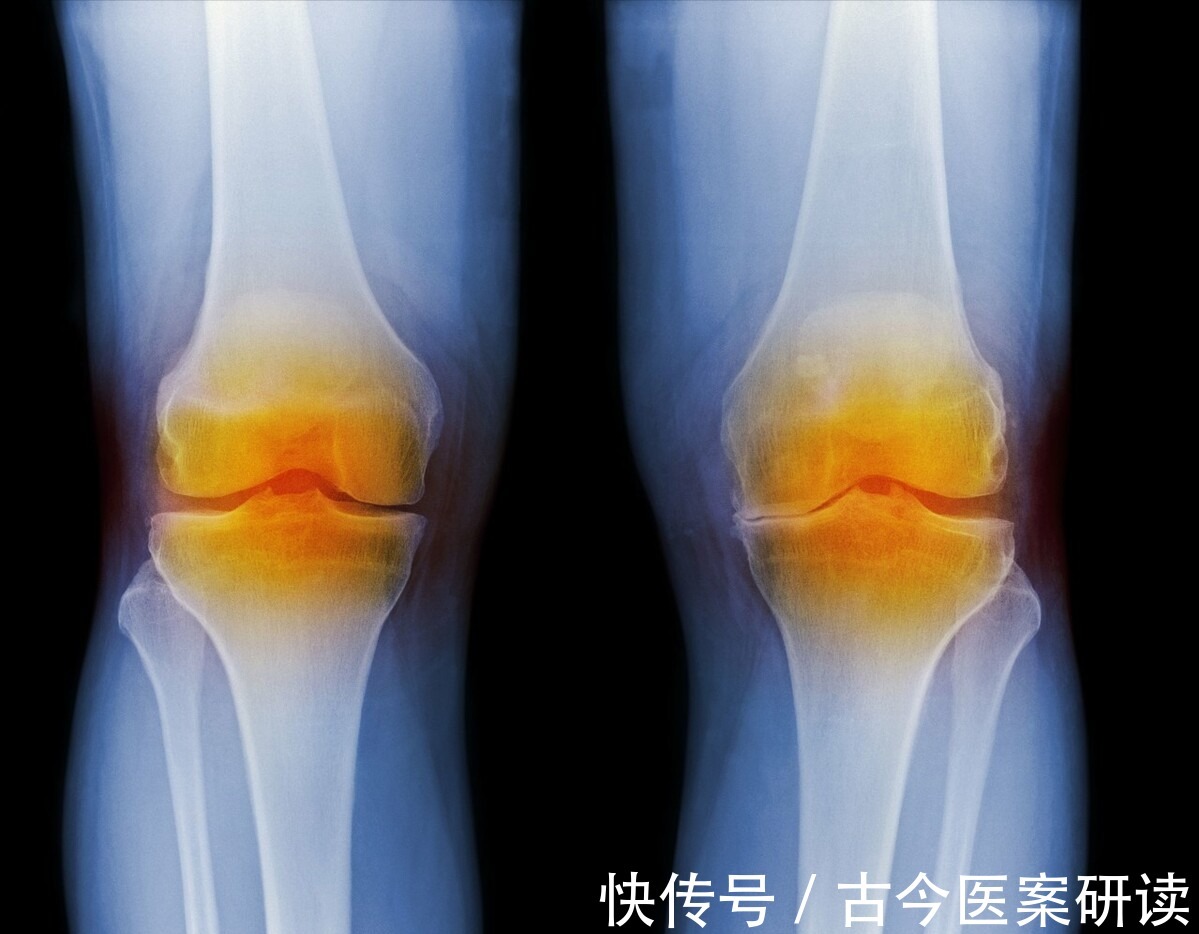

我看了下门诊拍的片子,确实见到胫骨平台关节面密度增高,应该是长期研磨、挤压所致。

借着这个诊疗小故事,我们来聊一聊膝关节骨性关节炎。

1.什么是膝关节骨性关节炎

本来我们大腿和小腿通过膝关节的支点,磨合可以很好地匹配,完成各种动作。

现在骨性关节炎了,不行了。

这病有轻有重,轻的只是酸痛,重的就要换人工膝盖了,没法修了。上面这老太属于中间吧。

它常见的表现有大腿与小腿连接处的软骨片磨坏了,不平整了,裂了,不光滑了;关节的内表面是有滑囊的,可以分泌一些润滑液,帮助润滑关节,就像车辆的机油一样,现在滑囊增生了,变厚了,变得了变得不滑了,还可能跑到关节间隙内;大小腿的两块骨头摩来摩去,也容易出现发炎、增生,这些增生的骨头也会卡住关节的活动。

这些原因长期影响,从而出现了膝关节的疼痛,没办法正常的屈伸。